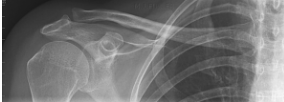

is this a normal or dislocated shoulder? in which direction is it dislocated?

dislocated, anterior